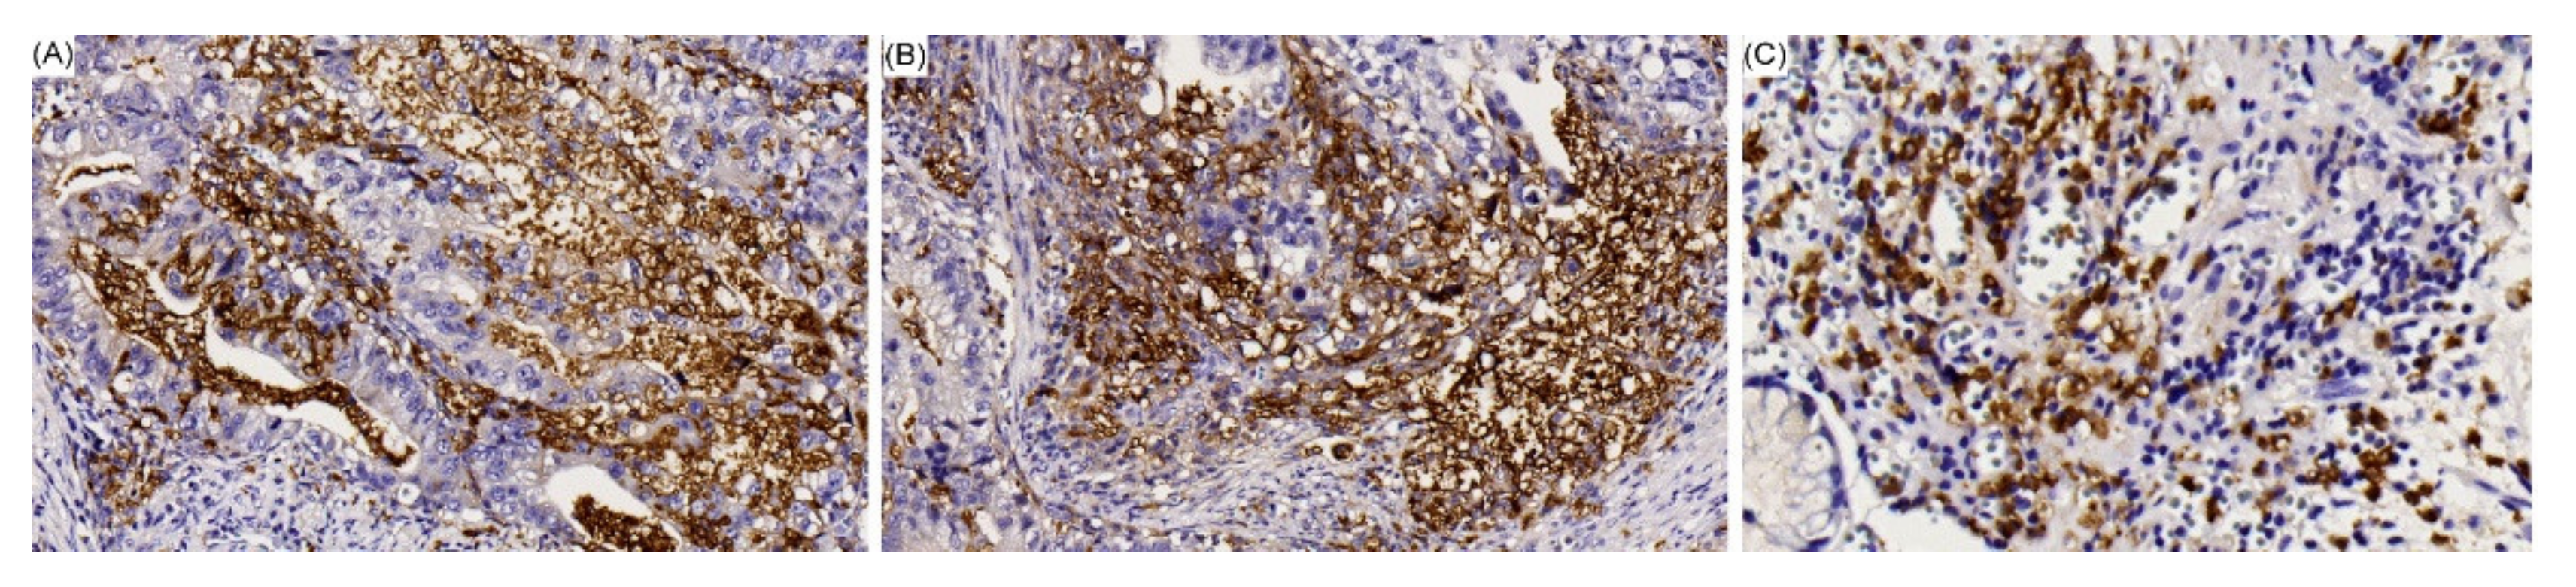

2.1. Clinicopathologic Characteristics

4.4. EBV Detection

4.5. Mutation Analysis of GC-Related Genes Based on MassARRAY

4.7. IHC Staining of PD-L1